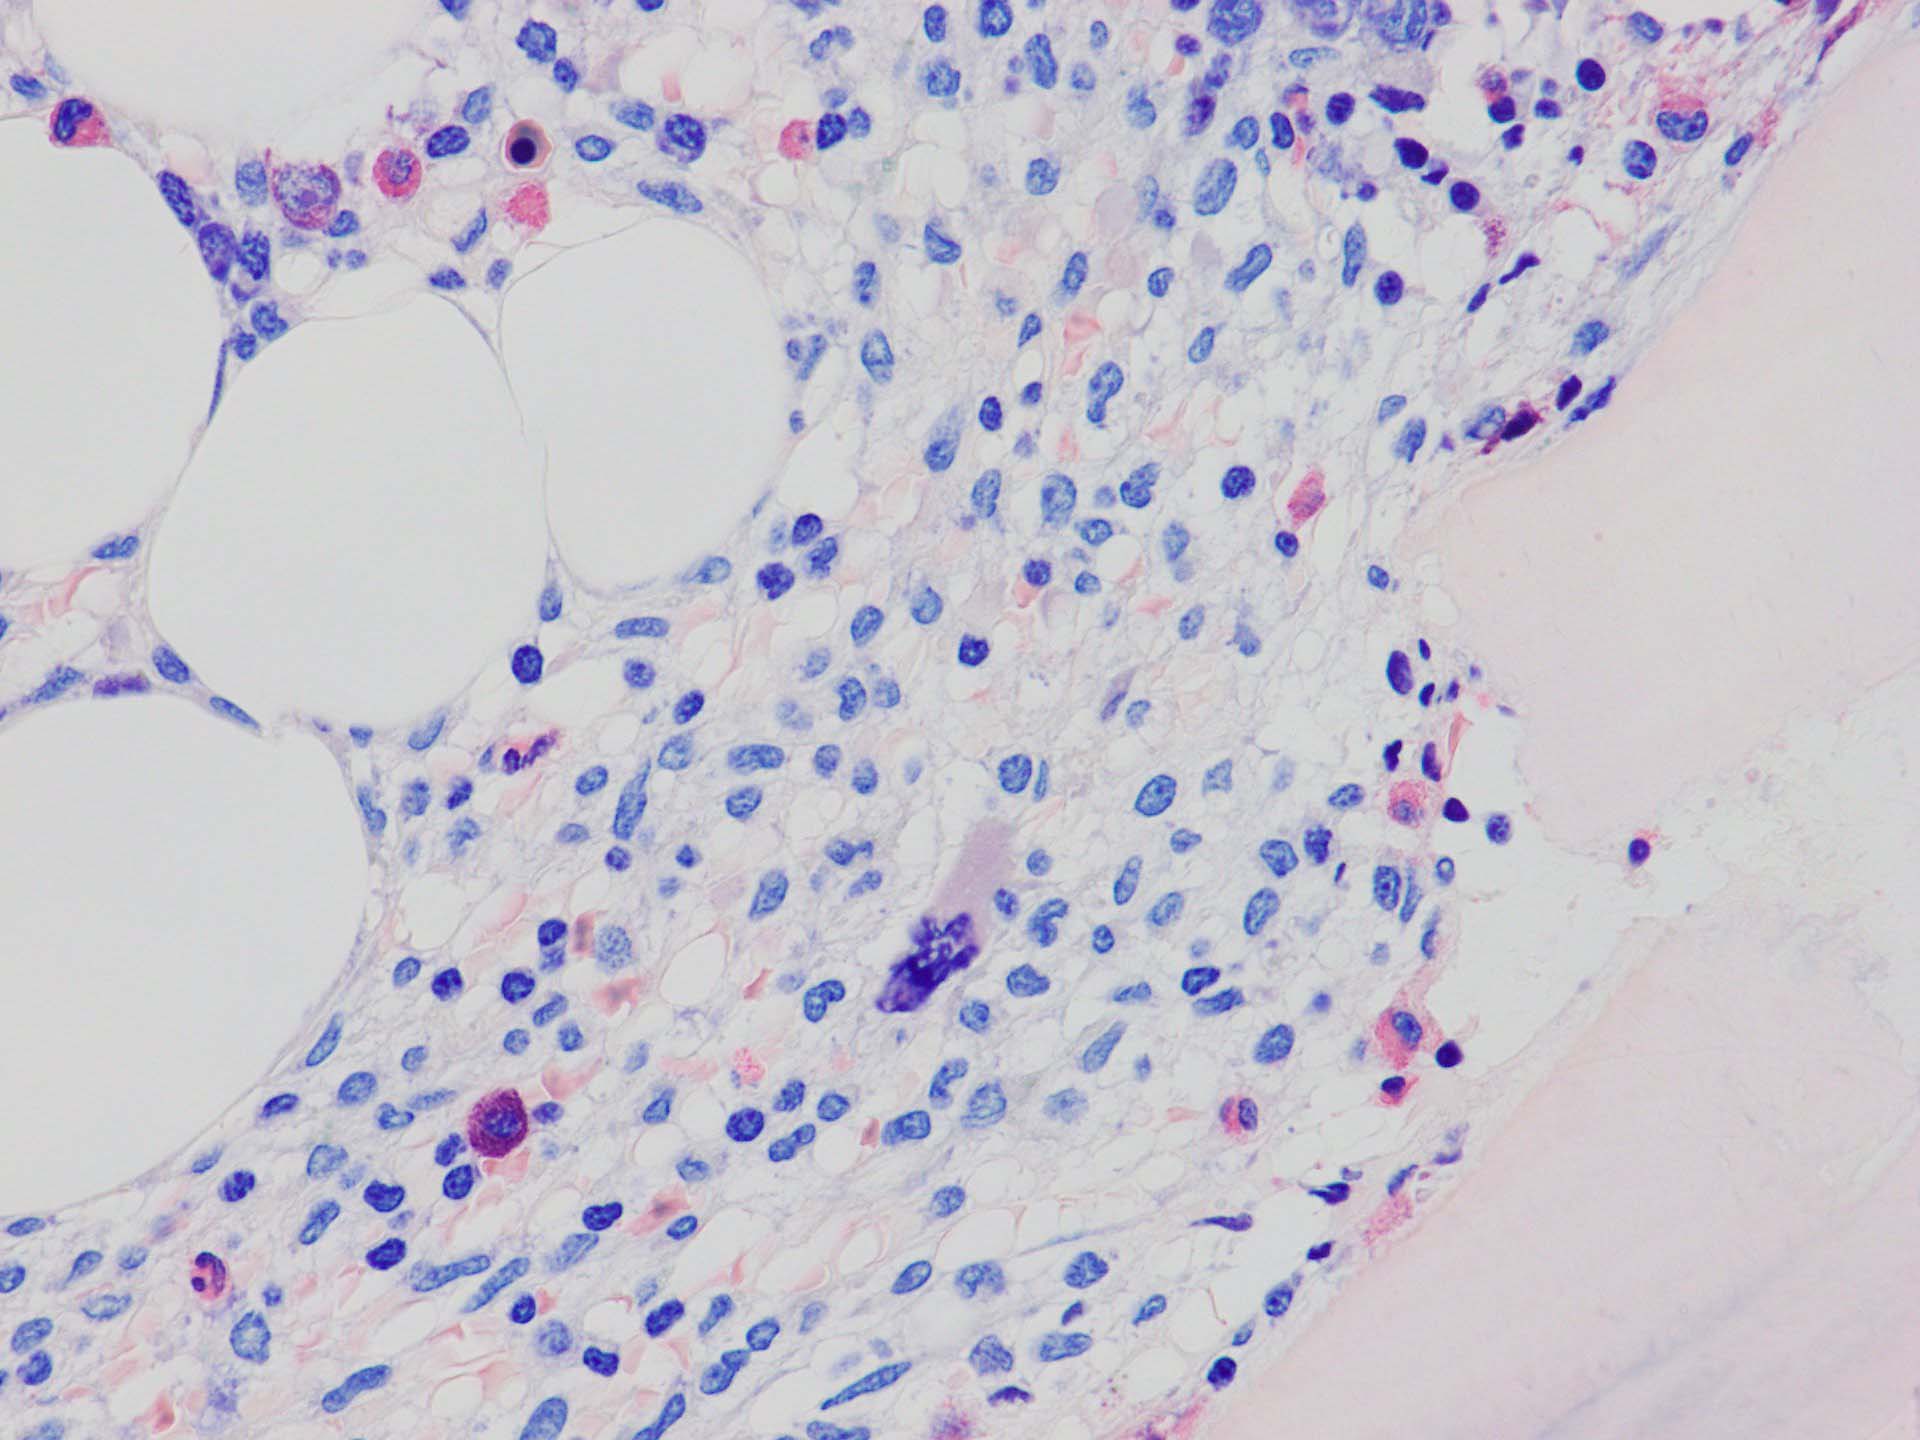

ASD-Giemsa陰性の細胞がシート状に増殖する. 核はクロマチン濃染, 核小体は不明瞭.類円形, 卵円形, くびれを持つ多稜形核, 長円形いびつで屈曲した核, など多彩. 細胞質は淡清色調, 広く淡明. 赤芽球血島は幼若赤芽球のみで形成される異形成像を示す. やや離れて成熟赤芽球が疎な集簇を示す.

Ag染色では, 疎な弾性線維が増生し,増殖細胞を小胞巣状に分画するいわゆる「lymphomatoid pattern」を呈する. 本例では, Mgkに異形成所見がある.

ASD-G 低倍率所見では赤芽球血島は幼若赤芽球の集簇巣が散在する, 顆粒球系細胞(ASDに赤く染色される)は減少,granulopoietic hypoplasiaを呈する.疎な集簇を示すmast cellsの増加がある.

ASD-G陰性の細胞がびまん性に増加しているように見える.